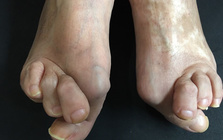

靴の健康被害、外反母趾。

外反母趾の痛みで悩む方が多いのですが、それ以上に・・・

外反母趾の痛み・・・

外反母趾の問題は痛みだけではありません。

その変形症状から多くの身体の不具合と

ほかの症状、病気を発症させてしまう方、